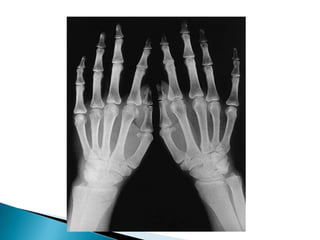

localizada: Nódulos deHeberden; Nódulos de Bouchard; Rizartrosis del pulgar; Gonartrosis; Coxartrosis; otras.